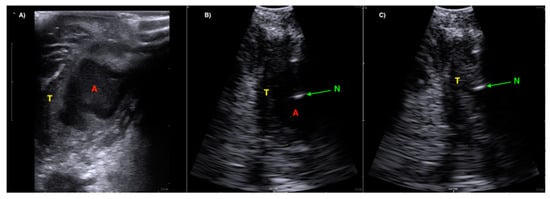

A Novel Technique for Intraoral Ultrasound-Guided Aspiration of Peritonsillar Abscess

2. Materials and Methods

3. Results